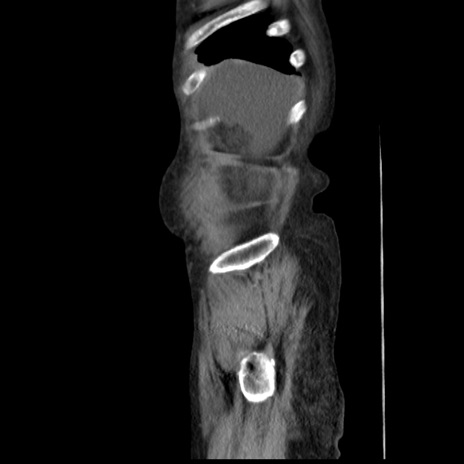

症例31(矢状断像)

【症例】80歳代 女性

【主訴】腹部膨満感

【現病歴】他院にて肝硬変にてフォロー中。1週間前から便秘、腹部膨満感、臍部腫瘤あり受診となる。

【既往歴】肝硬変

【身体所見】腹部膨隆あり、皮膚変化なし、疼痛なし。

【データ】WBC 4600、CRP 0.25